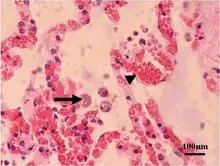

Acute toxoplasmosis is often asymptomatic in healthy adults.[13][14] However, symptoms may manifest and are often influenza-like: swollen lymph nodes, headaches, fever, and fatigue,[15] or muscle aches and pains that last for a month or more. It is rare for a human with a fully functioning immune system to develop severe symptoms following infection. People with weakened immune systems are likely to experience headache, confusion, poor coordination, seizures, lung problems that may resemble tuberculosis or Pneumocystis jiroveci pneumonia (a common opportunistic infection that occurs in people with AIDS), or blurred vision caused by severe inflammation of the retina (ocular toxoplasmosis).[15] Young children and immunocompromised people, such as those with HIV/AIDS, those taking certain types of chemotherapy, or those who have recently received an organ transplant, may develop severe toxoplasmosis. This can cause damage to the brain (encephalitis) or the eyes (necrotizing retinochoroiditis).[16] Infants infected via placental transmission may be born with either of these problems, or with nasal malformations, although these complications are rare in newborns. The toxoplasmic trophozoites causing acute toxoplasmosis are referred to as tachyzoites, and are typically found in bodily fluids.[17][18]

Skin

While rare, skin lesions may occur in the acquired form of the disease, including roseola and erythema multiforme-like eruptions, prurigo-like nodules, urticaria, and maculopapular lesions. Newborns may have punctate macules, ecchymoses, or "blueberry muffin" lesions. Diagnosis of cutaneous toxoplasmosis is based on the tachyzoite form of T. gondii being found in the epidermis.[31] It is found in all levels of the epidermis, is about 6 by 2 μm and bow-shaped, with the nucleus being one-third of its size. It can be identified by electron microscopy or by Giemsa staining tissue where the cytoplasm shows blue, the nucleus red.[32]

In its lifecycle, T. gondii adopts several forms.[33] Tachyzoites are responsible for acute infection; they divide rapidly and spread through the tissues of the body. Tachyzoites are also known as "tachyzoic merozoites", a descriptive term that conveys more precisely the parasitological nature of this stage.[34] After proliferating, tachyzoites convert into bradyzoites, which are inside latent intracellular tissue cysts that form mainly in the muscles and brain. The formation of cysts is in part triggered by the pressure of the host immune system.[35] The bradyzoites (also called "bradyzoic merozoites") are not responsive to antibiotics. Bradyzoites, once formed, can remain in the tissues for the lifespan of the host. In a healthy host, if some bradyzoites convert back into active tachyzoites, the immune system will quickly destroy them. However, in immunocompromised individuals, or in fetuses, which lack a developed immune system, the tachyzoites can run rampant and cause significant neurological damage.[33]